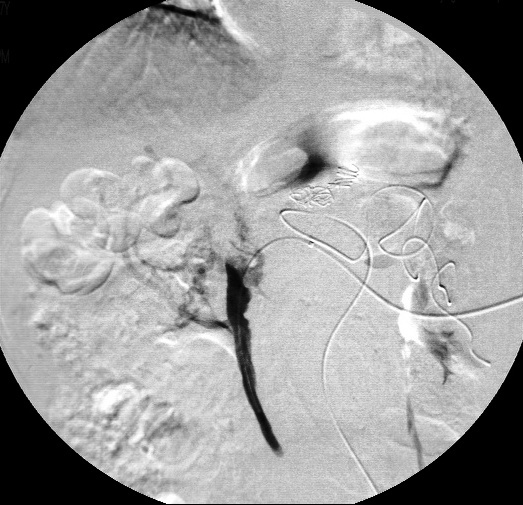

5、经皮冠状动脉造影

首先在动脉血管中撒些东西,再次穿越时光隧道,拍出心脏树状图,可将整个左或右冠状动脉的主干及其分支的血管腔显示出来,可对血管病变部位、范围、严重程度、血管壁的情况等作出明确诊断,决定治疗方案。

优点:是检查更是治疗

缺点:有创检查

诊断强项:冠心病

康康体检网称症状:胸痛,尤其情绪波动、劳累时

tips:检查是否患冠心病时的首选